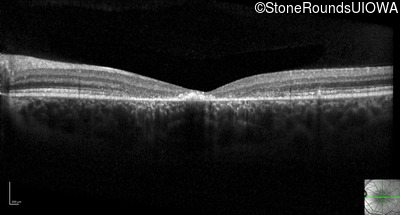

Optical Coherence Tomography - Left - 10/125 -2 sc

Exemplar / OCT Stack

OCT Stack